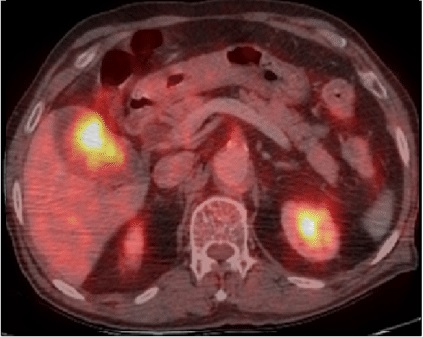

lymphadenopathie , lesion de l'extension hepatique et lesion metastasique .. .. La PET CT

est la technique d'utilise pour d'explorer de

l'extension de lesion et la metastase ..

Image de PET -CT en coupe axiale de meme

cas . Demontration de lesion vesiculaire

hypermetabolique susgestion de maligne |